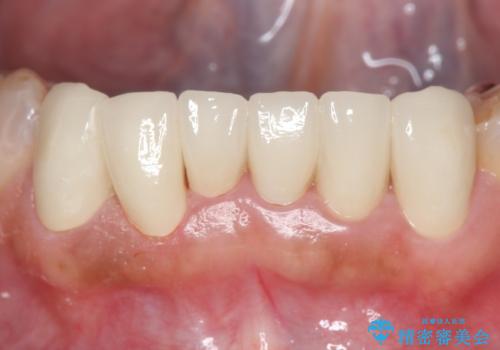

- 上下顎前歯部の見た目が気になるといらっしゃった方の症例です。

上顎は左4番から右4番までの8歯、下顎は左3番から右3番までの6歯、計14歯をオールセラミッククラウンにより補綴しました。

今回用いたオールセラミッククラウンはジルコニアフレームという白い素材の上にセラミックを盛っているため、審美性が非常に高いのが特徴です。